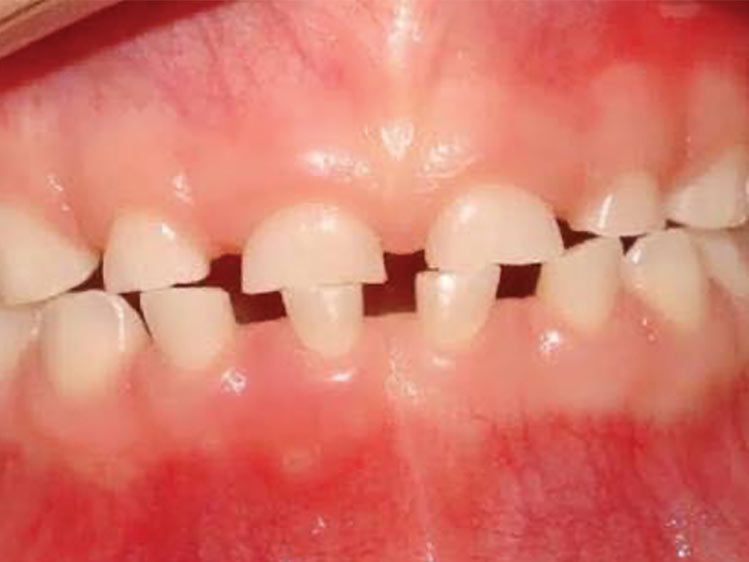

Nesse momento tão dinâmico da vida dos pequenos é importante acompanhar de perto as transformações, se certificando se estas mudanças estão acontecendo de forma correta.

Se algo estiver fora da normalidade, o problema poderá ser interceptado e corrigido prontamente, evitando longos tratamentos ortodônticos no futuro.